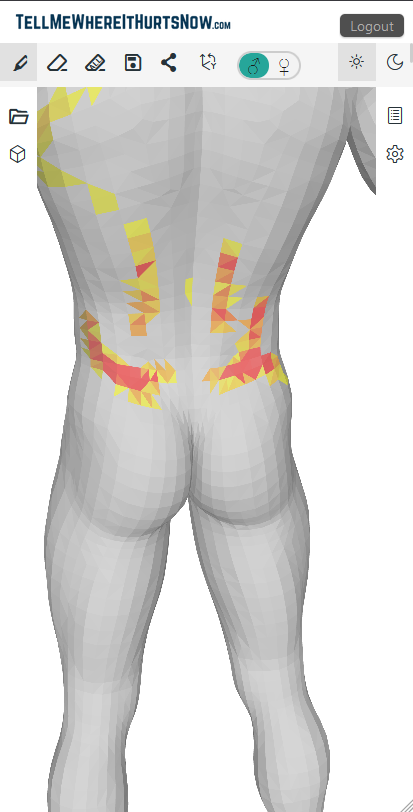

TellMeWhereItHurtsNow: Web app for visual pain communication. Mark areas on 3D body model, show intensity, share with doctors. Track pain over time. Works on all devices. Show doctors exactly where it hurts to improve communication and understanding.